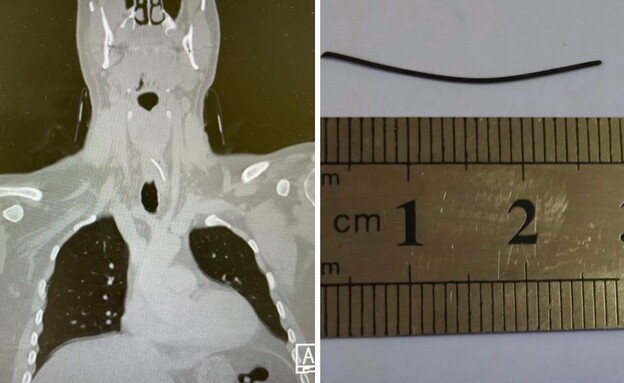

איכילוב: בת 4 עברה ניתוח להסרת גידול עצום מהריאהמיכל הלפרין | 13.11.25